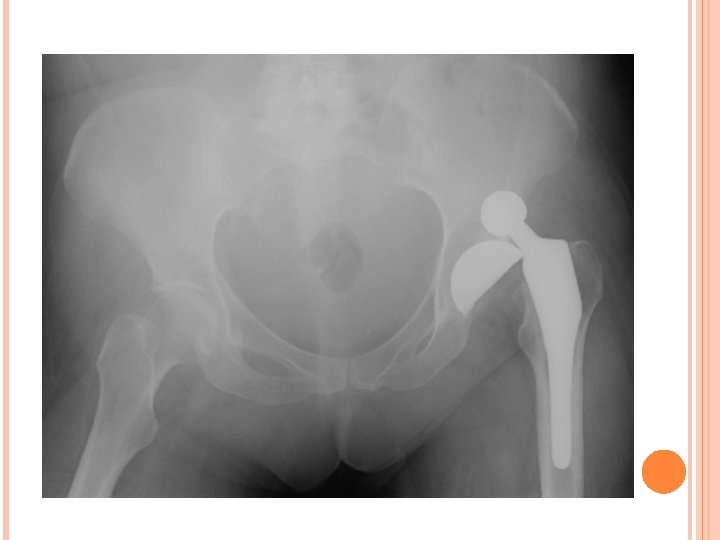

FEM FX CON’T Treatment – � Immobilized and transported for immediate medical care. Physician will either do a close reduction, or open reduction, depending on placement of fracture and number of fracture sites. ORIF (open Reduction Internal Fixation) requires pins and rods � Following surgery, ath will be immobilized in hinge brace and will require PT. Rehabilitation typically takes 4 months

ORIF – OPEN REDUCTION INTERNAL FIXATION